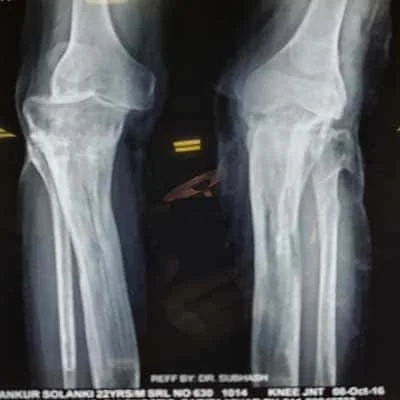

Complex Orthopaedic Surgery

• Removing the damaged articular cartilage (a plate that assists with smooth leg movement)

• Smoothening of the damage to the femur and tibia: These damages might be caused by degenerative diseases like arthritis.